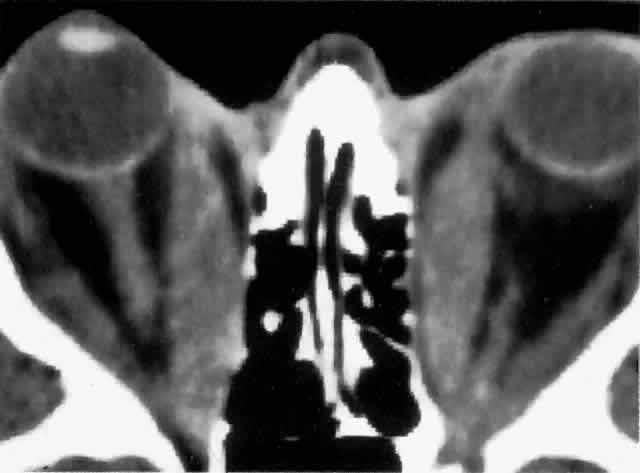

Computed tomography (CT), most revealing in the coronal plane, and ultrasonography are useful methods for assessing extraocular muscle thickness (Fig. 4). Magnetic resonance imaging (MRI) has been advocated as a means of differentiating between extraocular muscles that are actively inflamed and those that are fibrosed25–27; both muscular problems can restrict ocular movement, but the former is amenable to immunosuppressive intervention. The T2 relaxation time of MRI is directly proportional to the water content of the tissue scanned: since inflamed tissues are edematous, they should have longer T2 times. MRI is also thought to be better than CT in providing views of the orbital apex and may therefore be better for evaluating optic nerve compression.2